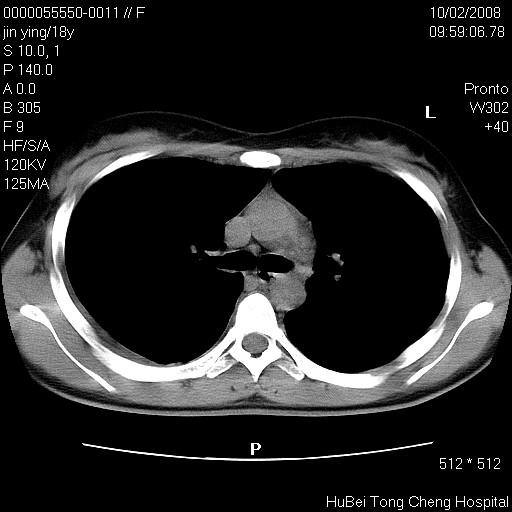

患者 女,18y。发热十余天,伴咳嗽。pe:t39⒈℃,bp 110/80mmhg,p 86次/min。神清,精神欠佳。双肺可闻及少许湿罗音。既往史不详。

临床诊断:肺部感染?

胸部ct轴位平扫(层厚10mm,螺距1.5,重建间隔10mm),图像如下: